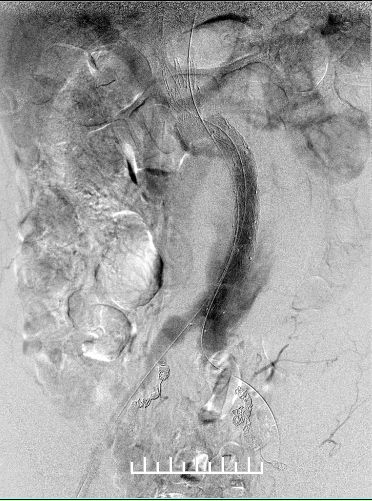

使用全穿刺技术(Preclose技术),建立双侧股动脉及右侧肱动脉入路。“全身像”显示:瘤颈成角约90度,左侧髂总动脉钙化扭曲严重,双侧髂内动脉显影,左侧髂内动脉瘤。